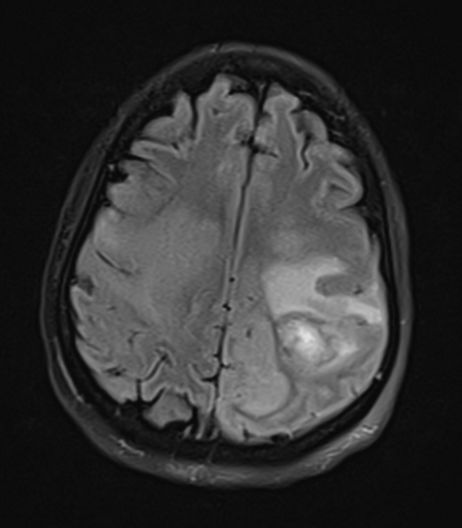

图3 40岁女性,脑脓肿,T2FLAIR像上可见病灶周围片状高信号区域,并呈手指状向周围延伸。